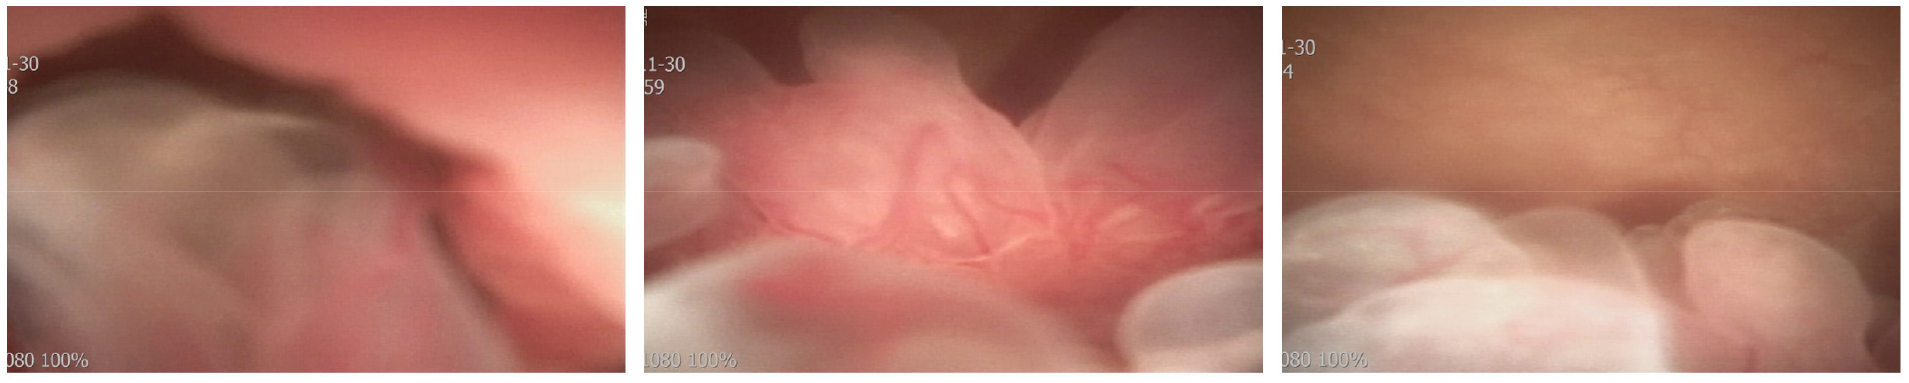

▶ 방광 내시경

명확한 진단을 위해 요도 및 방광 내시경을 시행하였다. 요도 및 요도 점막은 약간 지저분한 소견이 있었고 전립선 요도는 좁지 않았다. 초음파에서 보이는 양성 폴립형 종물이 방광목에 관찰되었다. 이는 bladder neck에서 trigone으로 이어져 있으며 병변이 상당히 넓었고 양측 요관의 입구는 잘 관찰되지 않았다.